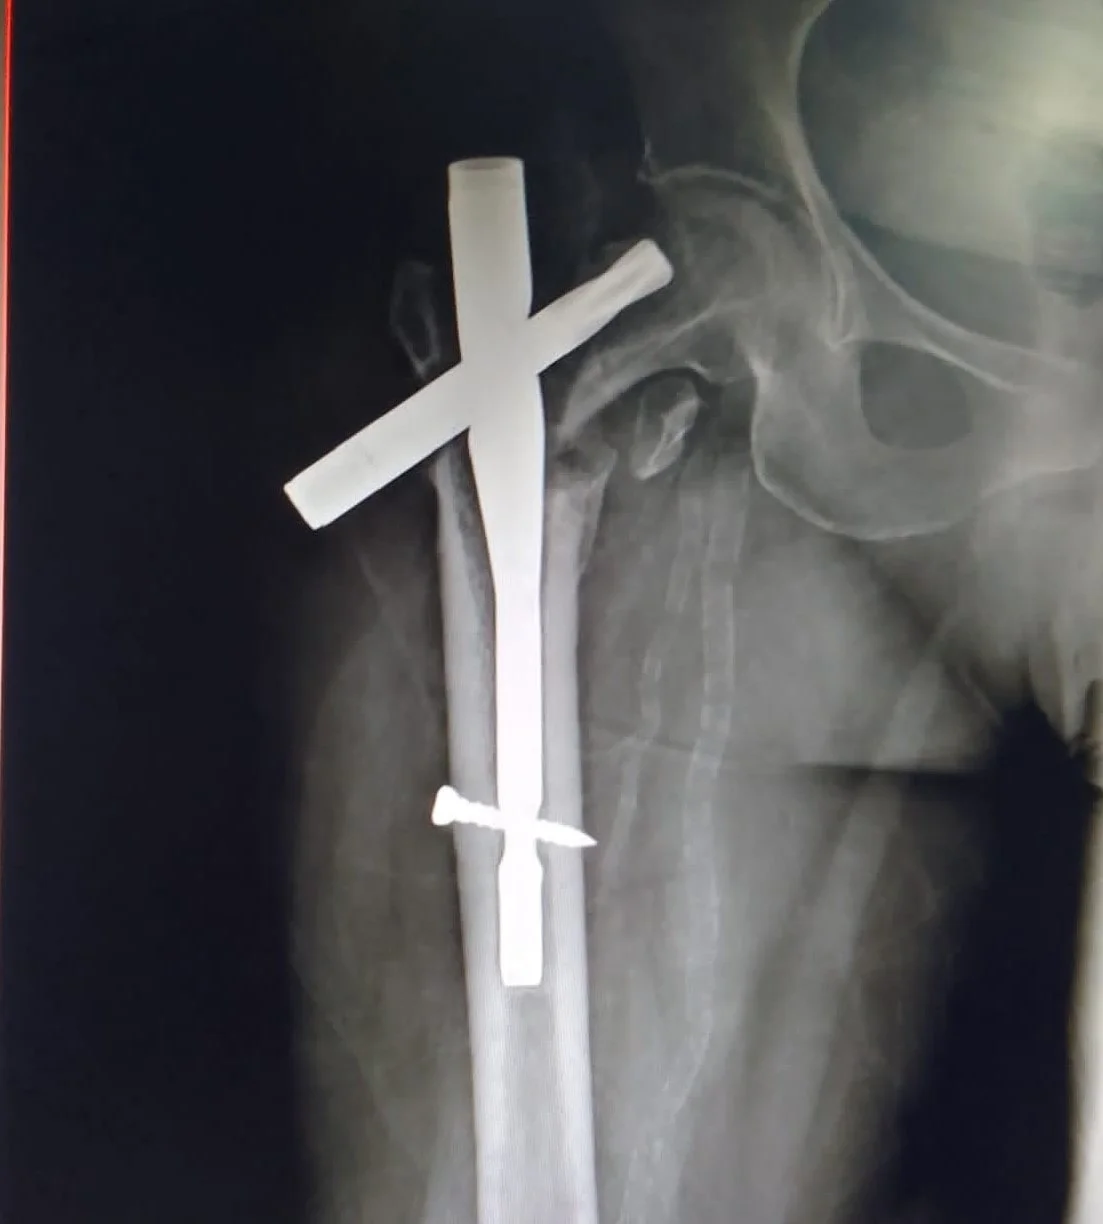

Failed hip fixation / Implant Cut out can also be effectively salvaged with Revision Total Hip Arthroplasty.